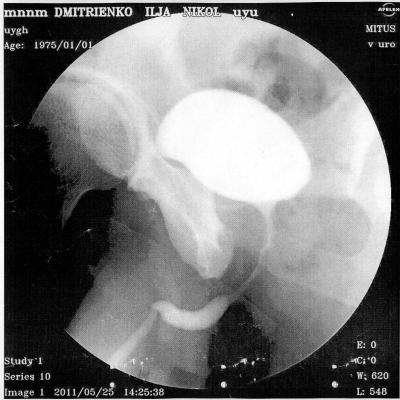

В начале 2011 года, в январе попал в , г. Алматы (был в командировке в Кзахстане)чеиспусканием, после проведенной уретроскопии, началось обострение, продержали в больнице неделю, вводили в/в антибиотики, была проведена инфузионно-детоксикационная терапия, физиолечение, делали восходящую и нисходящую уретроцистографии - б/о.

По приезду на Украину, боли не проходили в задней части уретры, было учащенное мочеиспускание, сдавал у местных урологов рахзличные анализы ПЦР на ЗППП - отрицательно, ОАМ, ОАК, различные посевы - все в пределах нормы. В конце марта сделал уже в г. Киева - КТ - на ней показало сужение простатической части уретры, было предложено бужирование, я отказался и поехал в Ростов, к профессору Когану, там провели исследования и сказали, что пока ничего не видят. Боли остаются, после полового акта боль усиливается, и учащается мочеиспускание. Не знаю, может быть болит семенной бугорок, могли задеть при уретроскопии, после которой и начались такие проблемы.